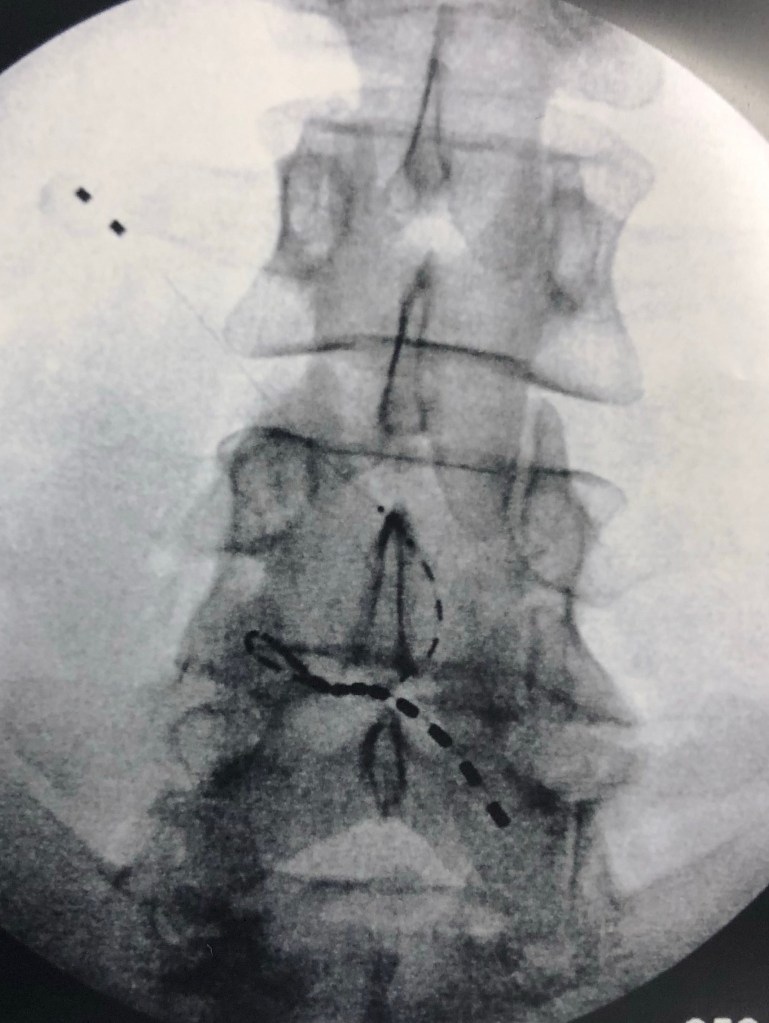

There had been some other things at play during 2019, including physical therapy and pain management. I had an amazing pain relief experience with a trial spinal stimulator that disrupts the pain signals to the brain. The week of relief had me walking pain free and excited to have a permanent implant and get on with life. The permanent implant procedure proved to be difficult. I was in surgery 2 1/2 times longer than planned and was sent home still half sedated! Within a short time frame after the permanent implant procedure, I was no longer getting relief. There were setting changes, equipment adjustments, but still no relief.

Not long after, an X-ray revealed the reason it wasn’t working. The implanted electrodes had moved and were pulled away from their intended location, taking with them the possibility of the much needed pain relief I was so hoping for.

The doctor said I would need another surgery to correct the problem. Why would I put myself through that again when it obviously wasn’t done correctly the first time? The process and time involved with all of it was not something I was willing to endure again. I was told I might want to consider alternative treatment but there was not much more they could do for me. Again, dismissed. The doctor got his money but who really paid the price?